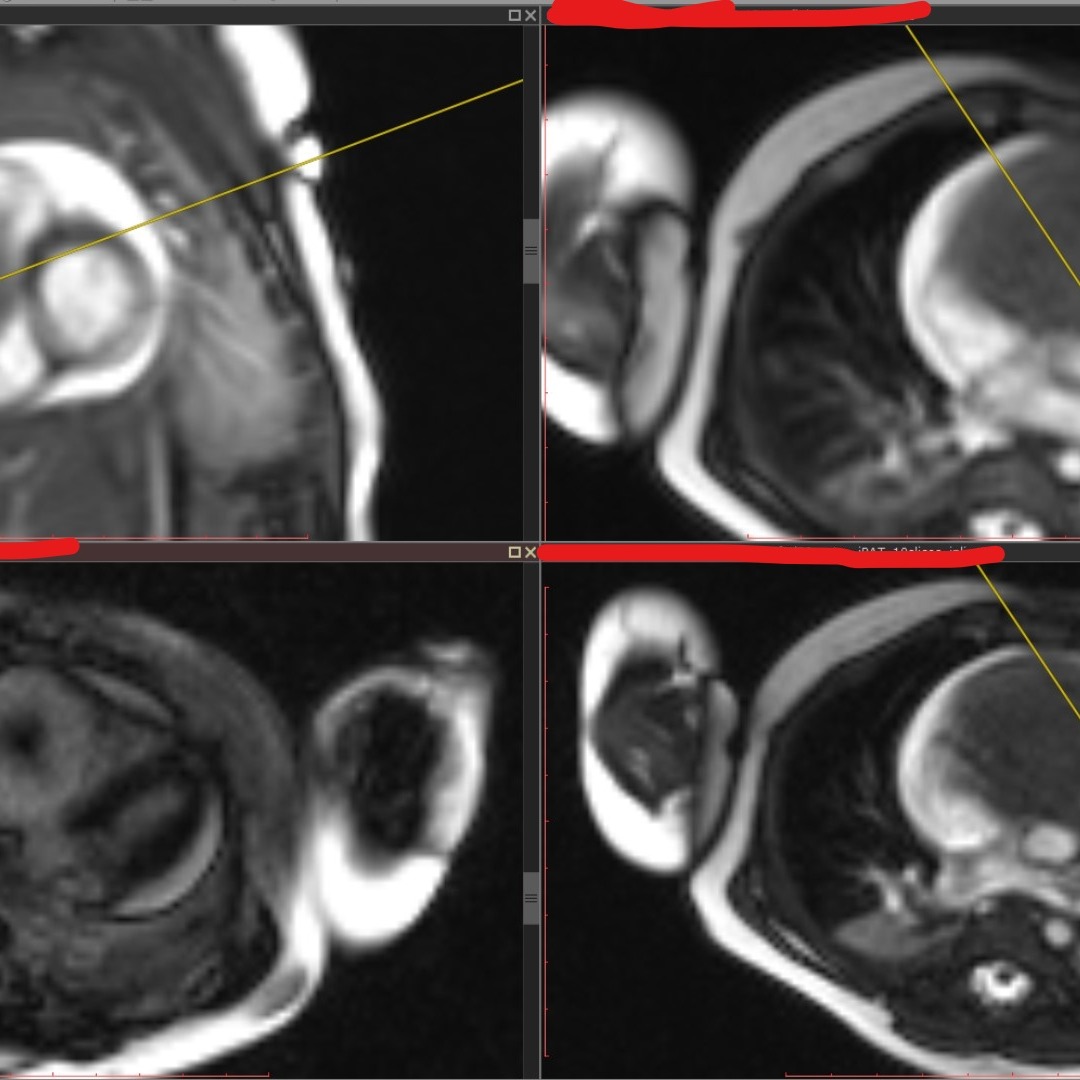

Выполняется трансторакольное ЭХОКГ исследование, которое позволяет заподозрить локализацию и размер опухоли, ее соотношение с другими анатомическими структурами сердца.